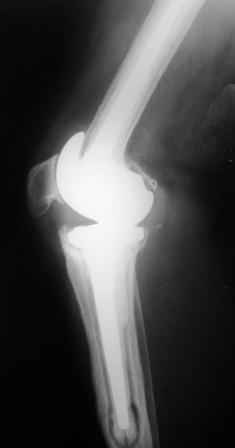

Уважаемые коллеги!Хотелось бы услышать Ваше мнение о возможности и способе помощи больной. 1939 г.р. В 1995г. эндопротезирование правого коленного сустава протезом Феникс, в 1999г. в г. Томске - ревизия - ротационный хинч W.Link. C 2005г. прогрессирует варусная деформация за счетнестабильности тибиального компонента. Попытка ортезирования - без эффекта. Попытка направить в ФСМУ без эффекта, да и больная не хочет никуда ехать.С уважением, Leonid

Понятно что для решения на операцию артродеза необходимы веские причины. Но я не уверен что здесь асептическое расшатывание. Судя по снимкам, бедренный компонент стоит не плохо, и есть рассасывание костной ткани вокруг всего протеза в голени. Что-то мне подсказывает об инфекционном процессе, возможно вялотекущем. В наших условиях я сделал бы обследование включающее анализы крови с СОЭ, СРБ. Сделал бы пункцию коленного сустава или даже биопсию мягких тканей для посева и микроскопии.